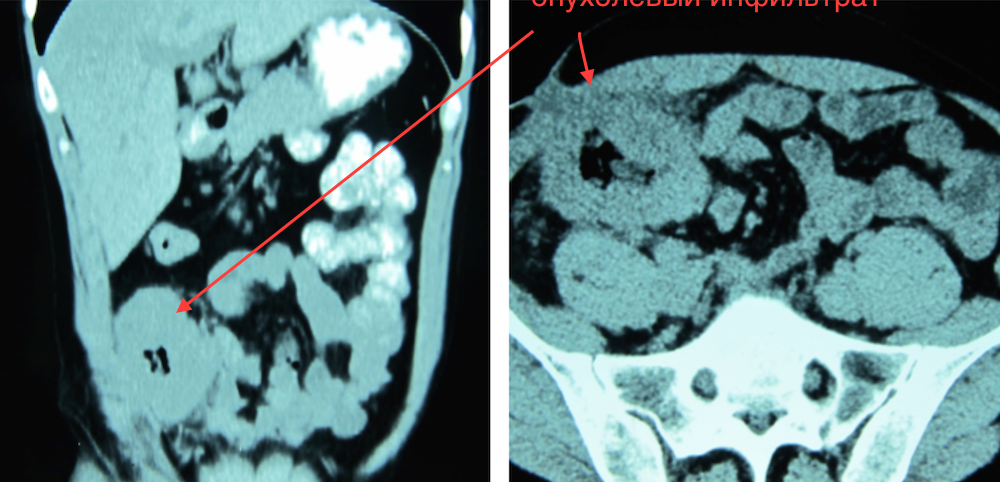

Рецидив рака слепой кишки

Отделение опухоли от наружных подвздошных сосудов и нижней полой вены